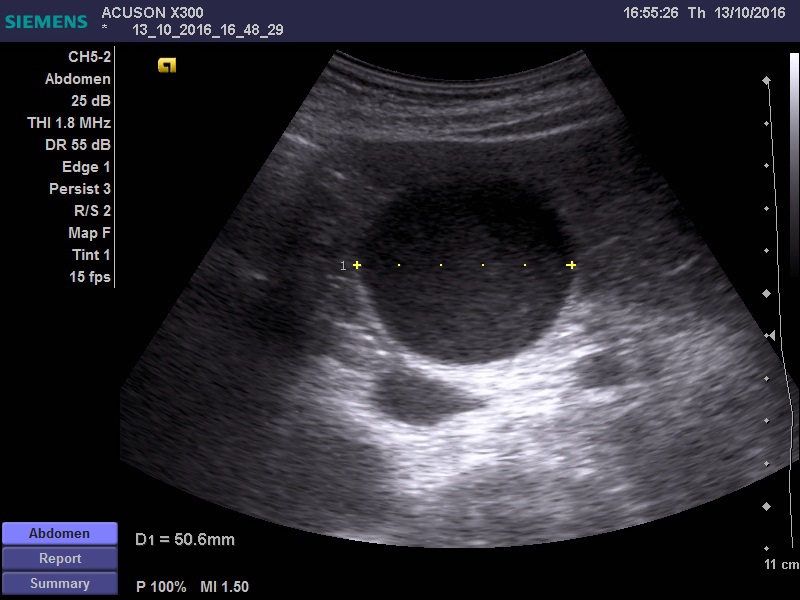

желчный пузырь увеличен 11*5 см, заполнен крупнодисперсной взвесью, в области шейки свободная жидкость. Дискинезия ЖВП?

Не видно причины гипертензии за уровне шейки ЖП -- холедоха, но признаки гипертензии есть.

есть признаки да. учитывая гемодинамически значимый стеноз ВБА, я бы склонился к эмпиеме пузыря, на фоне атеросклеротических изменений пузырной артерии. Учитывая возраст, клиника может быть стёрта, а учитывая наличие свободной жидкости, можно подумать о вялотекущей ишемии стенки и нарастающей деструкции. Я так бы рассудил.